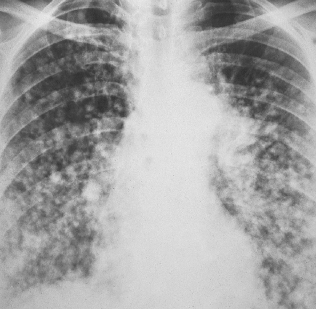

A 52-year-old woman (a nonsmoker) was hospitalized after experiencing a low-grade fever and dyspnea for a month. No abnormalities were noted on physical examination, but the chest film showed multiple nodules, both well- and ill-defined. Lung biopsy confirmed the diagnosis of bronchoalveolar carcinoma.

This neoplasm is considered a subtype of adenocarcinoma that arises from the terminal bronchioles and alveoli. It is seen predominantly in young women and is initially asymptomatic. The lesions are usually an incidental finding on a screening roentgenogram. Some patients have a history of cough, chest pain, increased dyspnea, low-grade fever, malaise, and weight loss.

(Case and film courtesy of Drs N. K. Akritidis, N. Georgogiannis, and C. Katsulidis.)